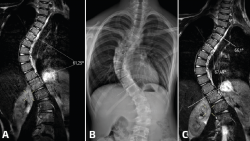

Figura 9. Resonancia magnética (RM) convencional en supino de columna completa en paciente con escoliosis (A); telerradiografía en bipedestación de columna completa (B); y RM en carga simulada del mismo paciente (C). Nótese el aumento del ángulo Cobb evidenciado en RM con carga simulada que se correlacionó con la radiografía en bipedestación.